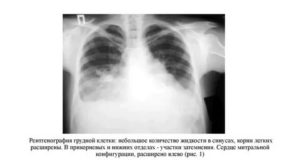

На представленной рентгенограмме лёгких визуализируется инфильтративная тень в наддиафрагмальной зоне слева. Корни тяжисты. Реберно-диафрагмальные синусы не завуалированы. Сердечная тень классической конфигурации. Патологии в мягких тканях не прослеживается.

Заключение: Рентген признаки левосторонней сегментарной пневмонии. Рекомендована рентгенография органов грудной клетки в левой боковой проекции для установки локализации затемнения.